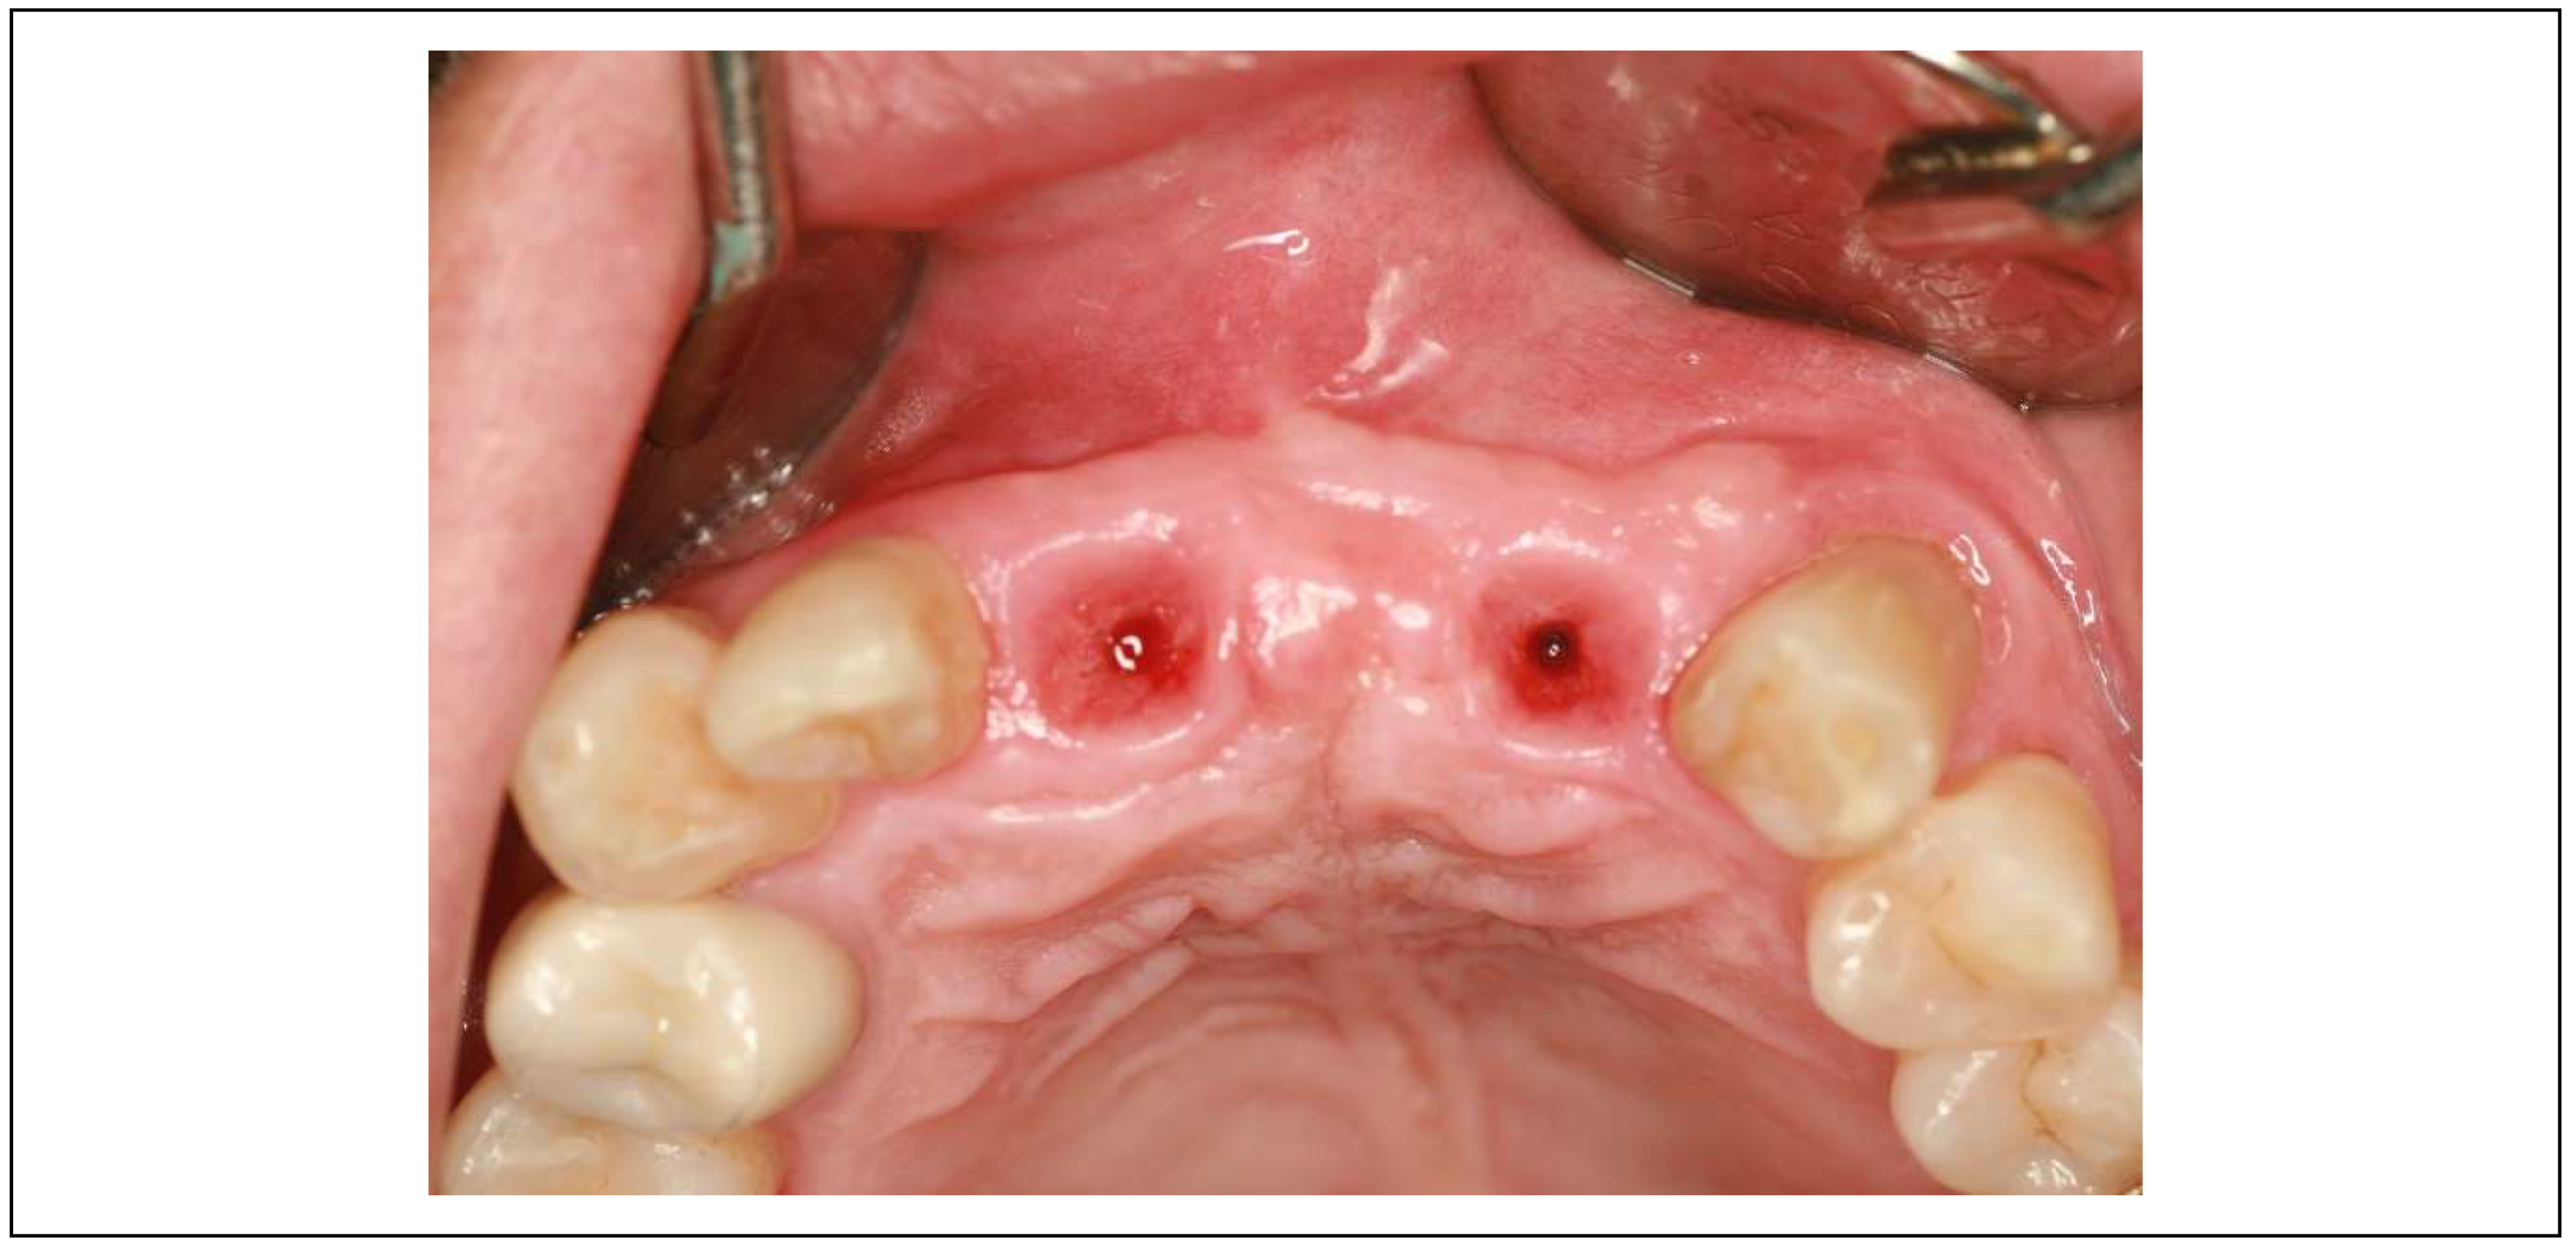

Among these, subcrestal implant placement (SPI) has gained attention for promoting bone remodeling and soft tissue stability, particularly in cases with thin peri-implant mucosa. Several studies have shown that subcrestally placed implants (SPIs) promote stable peri-implant conditions and minimize crestal bone loss. (

Figure 1) [

Figure 1.

Results after 10 years of subcrestally placed implants (SPI) – Fixtures were placed subcrestally, with X-rays showing no crestal bone loss and clinical photos demonstrating healthy peri-implant soft tissue and a natural emergence profile. This approach reflects a trend seen with Bicon implants during the 2000s to 2010s, where implant fixtures were often placed slightly deeper than those of other systems to support lasting stability.